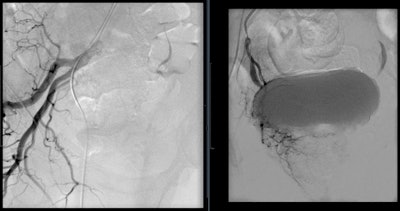

Prostate artery embolization is a noninvasive procedure that can bring long-term relief from symptoms caused by an enlarged prostate. This procedure works by closing the blood supply to the prostate, and, as a result, the prostate shrinks in size, reducing blockages and improving the symptoms.

Technically, PAE is challenging. Unnecessary catheterization increases procedure time and radiation exposure. Knowledge of anatomical features to identify and catheterize target arterial branches is paramount to achieve the best clinical outcomes. The prostate receives its arterial supply via the medial and the capsular/lateral branches but is variable among patients.

Assis et al proposed an angiographic classification of prostate artery anatomy and analyzed 286 pelvic sites to find that most inferior vesical arteries and their prostatic branches arise from the internal pudendal artery. Conebeam CT (CBCT) angiography has been utilized to evaluate the many variants of the prostatic artery. With direct contrast injection and 3D angiography, subtle prostatic feeders are better identified when compared with digital subtraction angiography and CT angiography.

Although the complications are minimal, PAE has adverse effects postprocedure. For patients without indwelling catheters, urethral burning during voiding and frequent urination have been the most common symptoms after PAE. However, these effects usually resolve within a week and can be treated with nonopioid analgesic medications. More serious complications are associated with nontarget embolization to the bladder, rectum, and penis. Ischemia to these organs is always possible and must be avoided through proper mapping via CBCT, microcatheterization for distal embolization, and calibrated microspheres for predictable embolization.